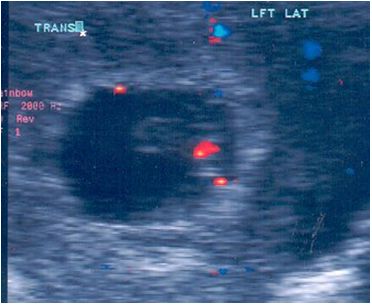

The aim of this study is to determine the relationship between placental /chorionic villi laterality and fetal genders early in pregnancy using 2-D ultrasonography and color flow Doppler.

This is a multi-center prospective cohort study of 5376 pregnant women that underwent ultrasonography from 1997 to 2007. Trans-vaginal sonograms were performed in 22% of the patients at 6 weeks gestation, and Trans-abdominal sonograms were used at 18-20 weeks gestation, at this time the fetal gender were confirmed in 98-99%. The fetal sex was confirmed 100% after delivery. The study also addressed the bicornuate uteri with single pregnancy in relation to placenta / chorionic villi location. The result was tabulated according to gender and placenta / chorionic villi location. Bicornuate uteri with single fetus in different horns were studied and tabulated

Dramatic differences were detected in chorionic villi / placental location according to gender. 97.2% of the male fetuses had a chorionic villi/placenta location on the right side of the uterus whereas, 2.4% had a chorionic villi/placenta location to the left of the uterus. On the other hand 97.5% of female fetuses had a chorionic villi/placenta location to the left of the uterus whereas, 2.7% had their chorionic villi/placenta location to the right side of the uterus.127 cases were found to involve bicornuate uteri with single foetuses, most male fetuses were located in the right horn of the uterus and showed right placental laterality (70%). Most female fetuses 59% on the other hand, were located in the left horn and showed left laterality (59%).Moreover, most of the males located in the left horn exhibited right laterality (89%). Also most females located in right horn exhibited left laterality (976.4%). In addition this research indicated that there was a possible link between renal pyelectasis and placental location, and it might be used as a genetic soft marker.

Ramzi’s method is using placenta /chorionic villi location as a marker for fetal gender detection at 6 weeks gestation was found to be highly reliable. This method correctly predicts the fetus gender in 97.2% of males and 97.5% of females early in the first trimester. And it might be helpful to use as a genetic soft marker in relation with fetal pyelectasis.

FEMALE- LEFT SIDE

MALE- RIGHT SIDE